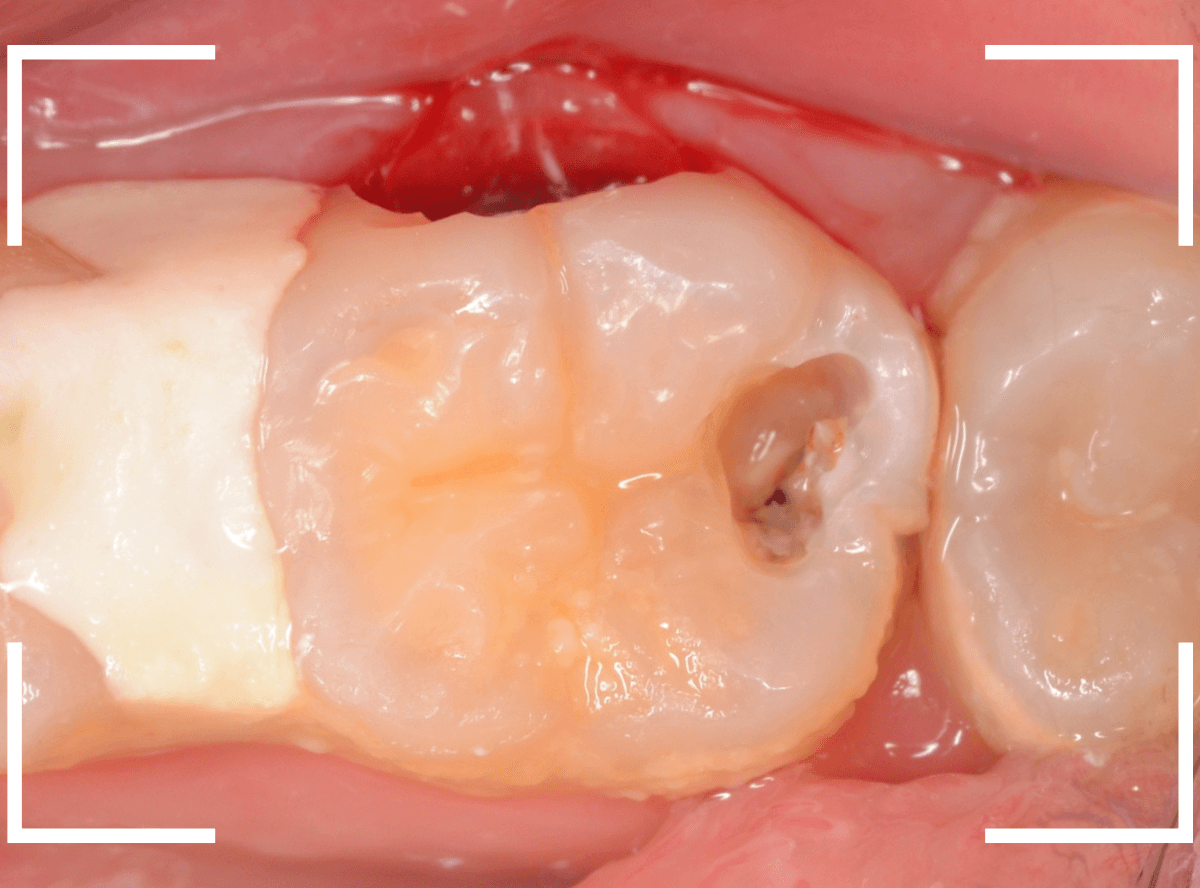

上の奥歯の虫歯が見つかった患者さんです。

初診のチェックの際に、上から目視すると、レジンがつめてある〇部分が薄暗く黒くなっているので、これは虫歯があるな、とわかりました。

レントゲン写真で確認します。

先ほどの黒く見えた部分は少し削るとすぐに虫歯が出てきました。

手前の歯まで虫歯を除去した時点で、う蝕検知液で確認します。

赤く染色されている部分が虫歯です。

思ったよりも深めの虫歯ですね。

レジンを除去して虫歯をすべて治療したところです。

レジンの中も全体にうっすらと虫歯になっていました。

このくらいの虫歯でも、患者さんは自覚症状はありませんでした。